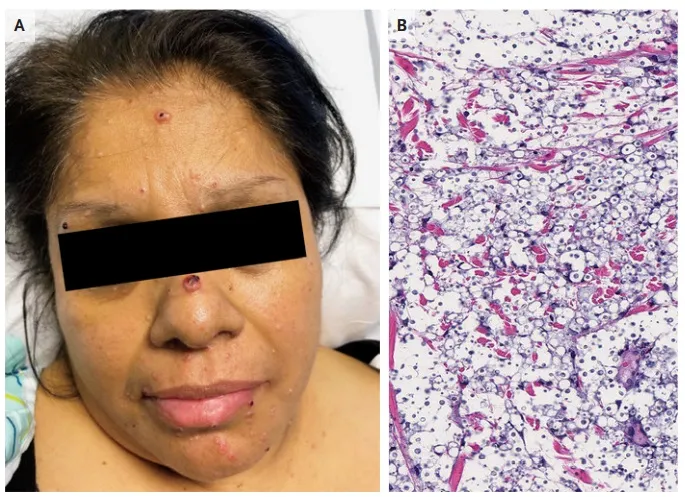

Proteinúria persistente, dor neuropática e lesões cutâneas podem parecer desconexas, mas, quando analisadas em conjunto, revelam a Doença de Fabry. Este caso ilustra como a integração entre clínica, biópsia renal, estudo enzimático e genética conduz a um diagnóstico preciso e a um manejo precoce, com impacto direto no prognóstico do paciente e de sua família.

Valkercyo Feitosa

11 meses atrás